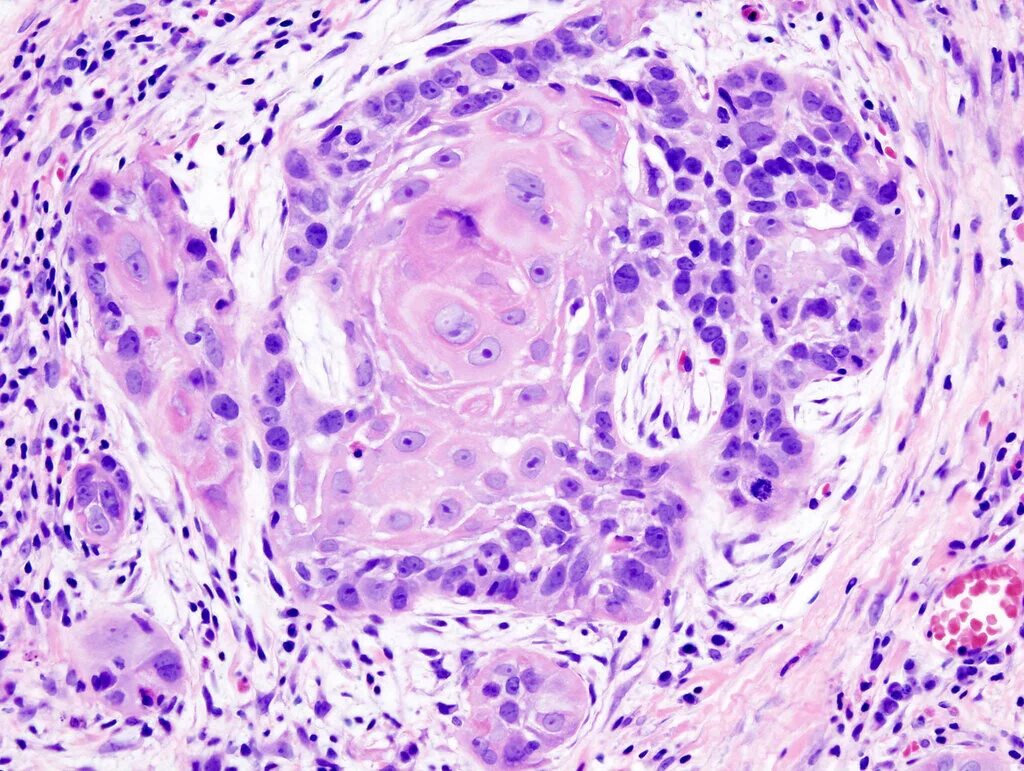

Плоскоклеточная опухоль